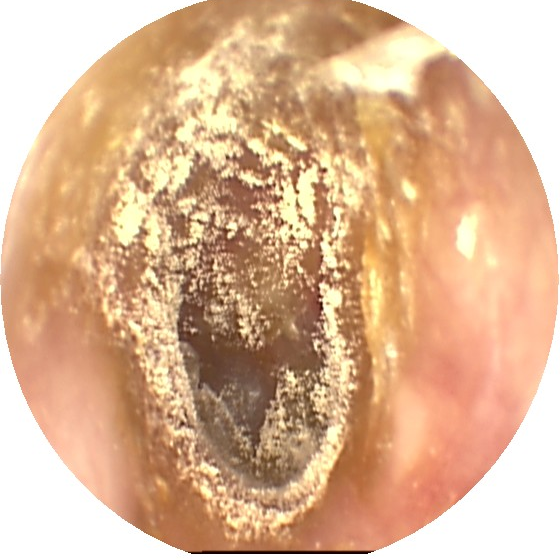

4、慢性化脓性中耳炎

慢性化脓性中耳炎是中耳黏膜、骨膜或深达骨质的慢性化脓性炎症,以间断流脓、鼓膜紧张部穿孔和听力下降为特点,常因急性中耳炎未获恰当的治疗迁延而来。

症状和体征

疼痛、反复流水流脓,听力受损,查体可见鼓膜穿孔伴分泌物。

治疗

控制感染,通畅引流,去除病因为其治疗原则。